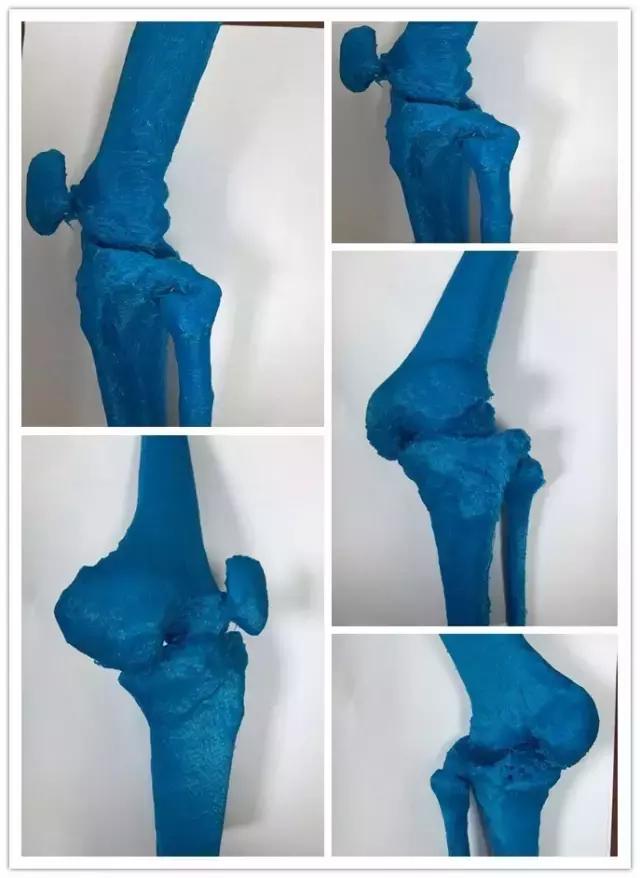

据骨外科李晖主任医师介绍:针对患者的严重关节畸形,天津医大总医院骨外科联合天津市骨研所应用患者CT数据利用3D打印技术,在术前1:1精确构建了患者膝关节的实体模型,并依此几经推敲制定患者的最适手术方案,在手术前应用Workshop模拟演练手术全程以完备细节。

术前Workshop演示手术,完备细节